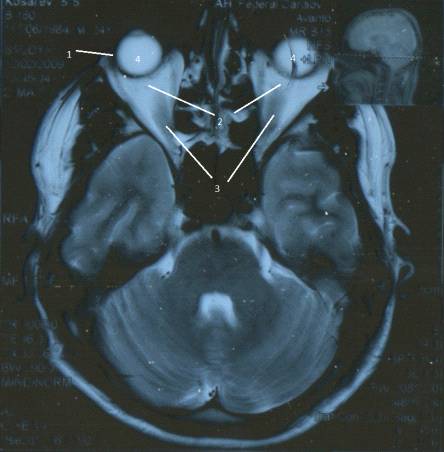

Рис. 5. МР-томограмма глаза в норме: 1 -

хрусталик; 2 - стекловидное тело глазного яблока; 3 - слезная железа; 4 -

зрительный нерв; 5 - ретробульбарное пространство; 6 - верхняя прямая мышца; 7

- внутренняя прямая мышца; 8 - наружная прямая мышца;9 - нижняя прямая мышца

Передняя камера содержит водянистую влагу,

вследствие чего дает выраженный гиперинтенсивный сигнал на Т2-ВИ. Хрусталику

свойствен выраженный гипоинтенсивный сигнал и на Т1-ВИ, и на Т2-ВИ, так как он

представляет собой полутвердое бессосудистое тело. Стекловидное тело дает

повышенный МР-сигнал на Т2-ВИ и пониженный - на Т1-ВИ. МР-сигнал рыхлой

ретробульбарной клетчатки имеет высокую интенсивность на Т2-ВИ и низкую - на

Т1-ВИ.